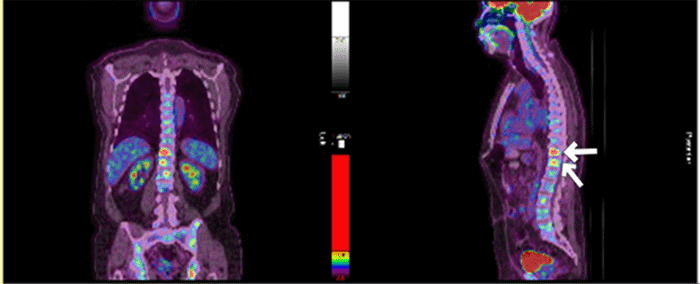

Pathologic examination confirmed chronic cholecystitis and identified a focal, transmural atypical lymphoid aggregate. Immunohistochemistry revealed the aggregate to be positive for CD20, CD23, BCL-2, and negative for CD3, CD30, BCL-1, and BCL-6. CD21 highlighted a scattered follicular dendritic cell meshwork (Figure 1). The Ki-67 proliferation index was low (5%). Molecular analysis demonstrated clonal B-cell immunoglobulin heavy chain gene rearrangement peaks in the FR2 and FR3 regions, with none detected in the TCR regions. These findings were consistent with a low-grade mature B cell lymphoma with gallbladder involvement.

Figure 1. Gallbladder Pathology. Published with Permission

A (H&E stain, 40x): Transmural infiltration of atypical lymphocytes with mixed morphology (small, intermediate, large size) and round to irregular nuclei with condensed chromatin. B (H&E stain, 400x): Higher magnification view of atypical lymphocytes. C (CD20 immunostain): Positive staining for CD20 highlights B-cell lineage of the atypical lymphocytes